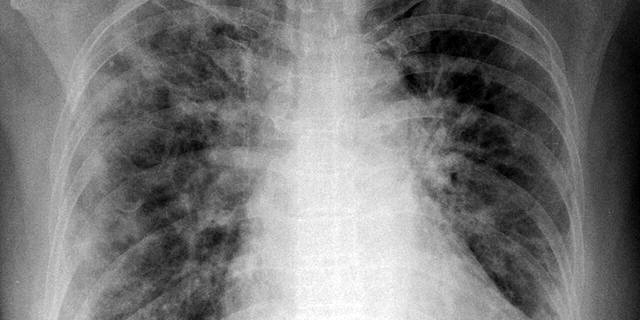

İlk değerlendirmelerin sonucunda hastaların %65,9’unda en az bir kalıcı semptom görüldü. Hastalar ağırlıklı olarak nefes darlığı ve öksürükten muzdaripti ve bilgisayarlı tomografi (BT) taramalarında akciğer hasarı tespit edildi. Çalışmanın yazarlarından Dr. Sabina Sahanic, bulgularını şöyle özetiyor: BT sonuçlarına göre çalışmaya katılanların %88’i ilk ziyarette hala patolojik bulgular gösteriyordu. İkinci ziyarette ise bu oran, %56’ya düşmüştü.

Bilgisayarlı Tomografi taramalarında ‘buzlu cam’ olarak bilinen beyaz lekeler olarak ortaya çıkan koronavirüsün akciğerlerde neden olduğu iltihaplanma ve sıvı hasarı altı haftada 74 hastada (%88) ve 12 haftada 48 hastada (%56) hala mevcuttu. Altı haftalık ziyarette, ekokardiyogramlar 48 hastada (%58) kalbin gevşeme ve genişleme noktasında (diyastol) sol ventrikül disfonksiyonuna sahip olduğunu gösterdi. Kalp hasarı, kan pıhtıları ve iltihabın biyolojik göstergelerinin tümü önemli ölçüde yüksekti.